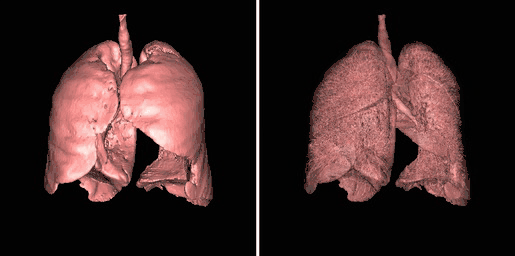

Surface rendering is also referred to as Shaded Surface Display (SSD) and involves generating surfaces from regions with similar voxel values in the 3D data as illustrated by the SPECT lung-perfusion scan shown in the left panel below:

3D surface rendering: shaded surface and wireframe display.

The process involves the display of surfaces which might potentially exist within the 3D voxel data on the basis that the edges of objects can be expected to have similar voxel values. One approach is to use a grey-level thresholding technique where voxels are extracted once a threshold value is encountered in the line of the projection – see the following diagram. Triangles are then used to tesselate the extracted voxels, as shown in the right panel of the figure above – and the triangles are filled using a constant value with shading applied on the basis of simulating the effects of a fixed virtual light source – as shown in the left panel above.

Illustration of surface rendering.

An opacity table can be applied to the results so that surfaces from internal features can also be visualized. As an example, two surfaces have been identified in the following image from the CT scan where voxel values from bone surfaces are coded in an opaque yellow colour and tissue surfaces in a transparent shade of red.

SSD of two surfaces.

A second example of using an opacity table is shown in the following figure. Here, axial CT data from the patient's airways have been segmented using a region growth technique and the result processed using surface rendering, with full opacity as shown in the left panel and with a reduced opacity (30%) as shown in the right panel:

3D SSD: opaque and transparent display.

Notice that internal features of each lung can be discerned when the opacity is reduced. Notice also that continued viewing of this type of transparency display can generate apparent reversal of the image rotation, similar to that noted for the 3D MIPs above. One method of overcoming this type of problem is to segment each lung, for instance. and to blend the results, as illustrated in the following figure:

3D SSD: blending of each lung following segmentation.